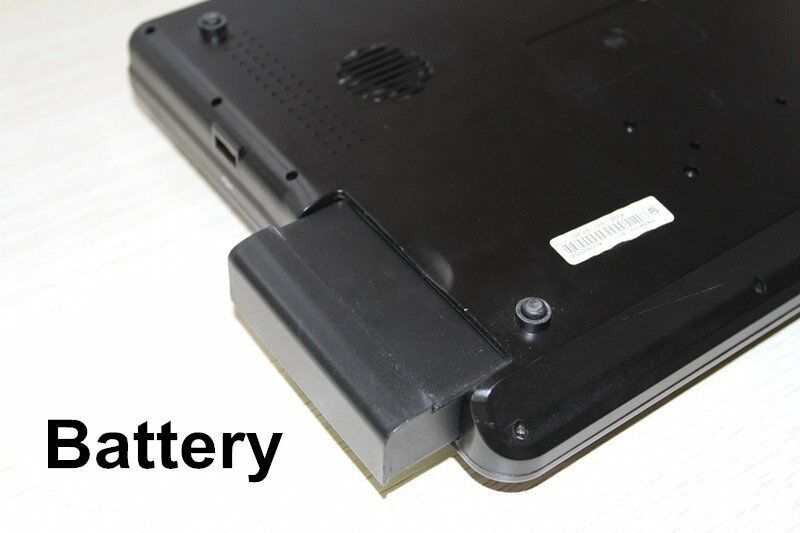

One of the key features of this ultrasound scanner is its portability. Because medical professionals often need to move between different locations, having a lightweight and portable device significantly enhances their ability to perform diagnostics on-the-go. The laptop design allows for easy transport and setup, so you can start scanning in minutes. Additionally, the digital technology integrated into this machine guarantees more precise and reliable readings compared to older models.

Moreover, the durability and build quality of the Newest Digital Portable Laptop Ultrasound Scanner ensure that it can withstand the rigors of daily use. It's crafted with materials that resist wear and tear, so you can rely on it for consistent performance over time. The 7.5MHz Linear probe is also designed for longevity, providing clear and consistent images throughout its usage life.